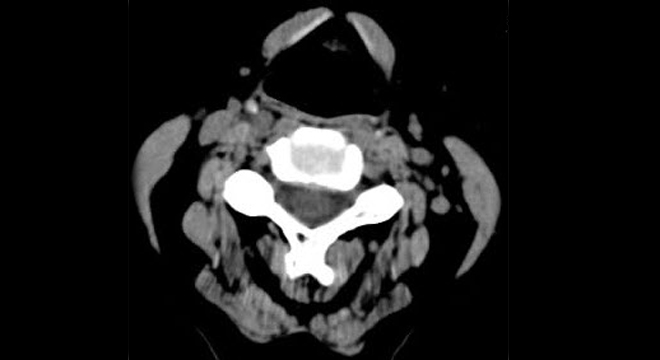

• Röntgenuntersuchung der Wirbelsäule

• Bei Verdacht auf Bandscheibenbeteiligung Magnetresonanz-Tomographie (MRI)